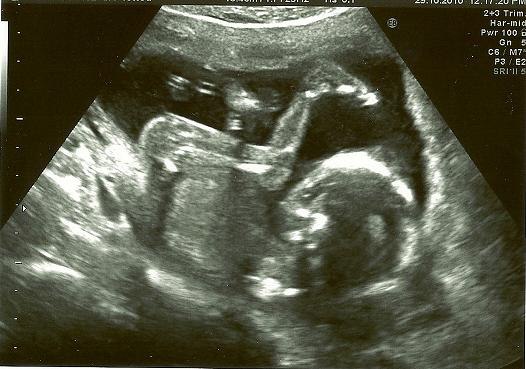

Alt var helt perfekt til scanningen og baby lå som en rigtig gymnast med knæerne helt oppe ved næsen hihi!

der er stadig tvivl om køn men lægen tror på pige

og et billede af mit vidunder

Vedhæftede fotos (klik for at se i fuld størrelse)